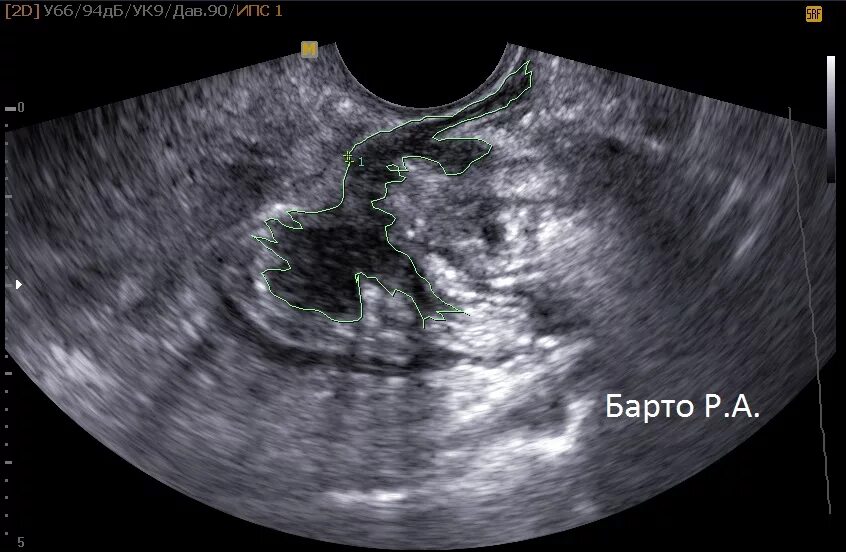

Узловая форма аденомиоза матки на узи. узи эндометриоз эндометриоз. диффузный эндометриоз матки узи.

Миометрий диффузно неоднородный эндометриоз. аденомиоз узловая форма узи. внутренний эндометриоз на узи. узи критерии внутреннего эндометриоза.

Узи критерии внутреннего эндометриоза. узловая форма аденомиоза по узи. аденомиоз узловая форма узи. узи узловой эндометриоз.

Узловая форма аденомиоза по узи. узловая форма аденомиоза матки на узи. диффузный эндометриоз матки узи.

Узловая форма аденомиоза матки на узи. диффузный эндометриоз матки узи.

Узловая форма аденомиоза матки на узи. узловой аденомиоз матки на узи. аденомиоз узловая форма узи. узловая форма эндометриоза матки.

Аденомиоз диффузная форма узи. аденомиоз узловая форма узи картина.